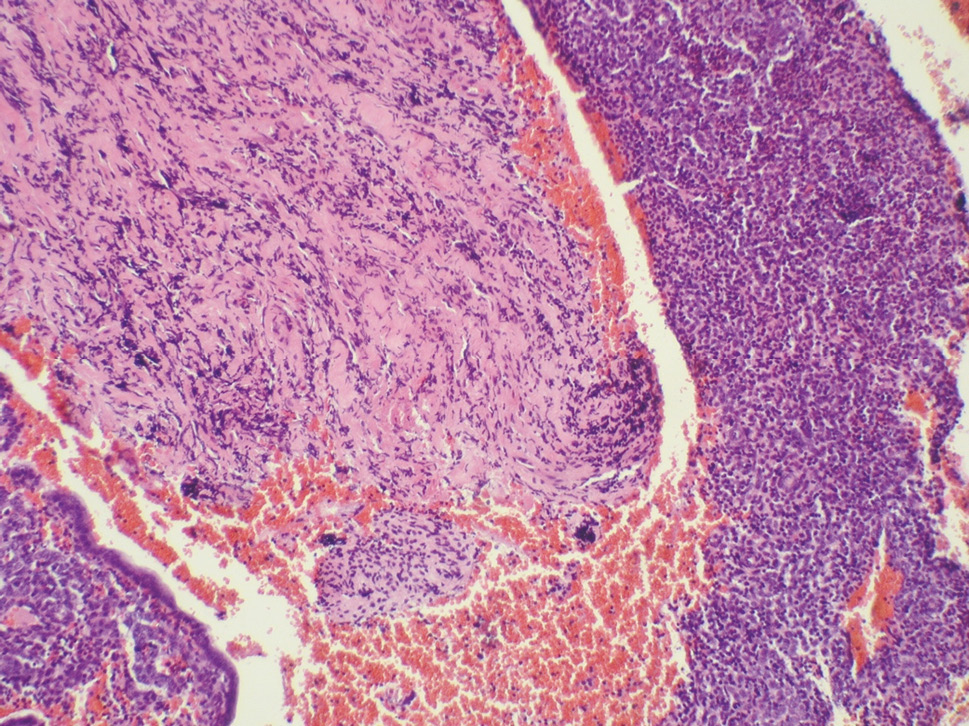

In all the cases, the visualized endometrium did not correspond to the phase of the ovarian-menstrual cycle, and as a rule, it was thickened, bright pink in color, and with various folds. Transparent points were determined, which indicated an increased number of glandular ducts. When assessing the prevalence of the pathological process, diffuse hyperplasia was diagnosed in 61.3% of patients, and focal hyperplasia was found in 38.7% of cases. According to the morphological study, most patients had simple hyperplasia without atypia (87.67%), and complex endometrial hyperplasia without atypia was detected in 12.33% of cases. Glandular hyperplasia was characterized by a sharply thickened endometrium with an elongated and convoluted shape of the glands. Histological examination revealed an increase in the concentration of glands in the cytogenous stroma, which was uneven. The glandular epithelium was similar in structure to the endometrial epithelium of the proliferation stage, and mitotic figures were found (Fig. 1).

Fig. 1. Endometrial hyperplasia without atypia in women of reproductive age (hematoxylin and eosin staining at ×100 magnification)

Рис. 1. Гиперплазия эндометрия без атипии у женщины репродуктивного возраста (окраска гематоксилином и эозином, увеличение ×100)

There were no signs of cell atypia in the test material in such patients. In a number of cases, a polypous form of glandular endometrial hyperplasia without atypia was revealed, characterized by the formation of many polypous outgrowths.